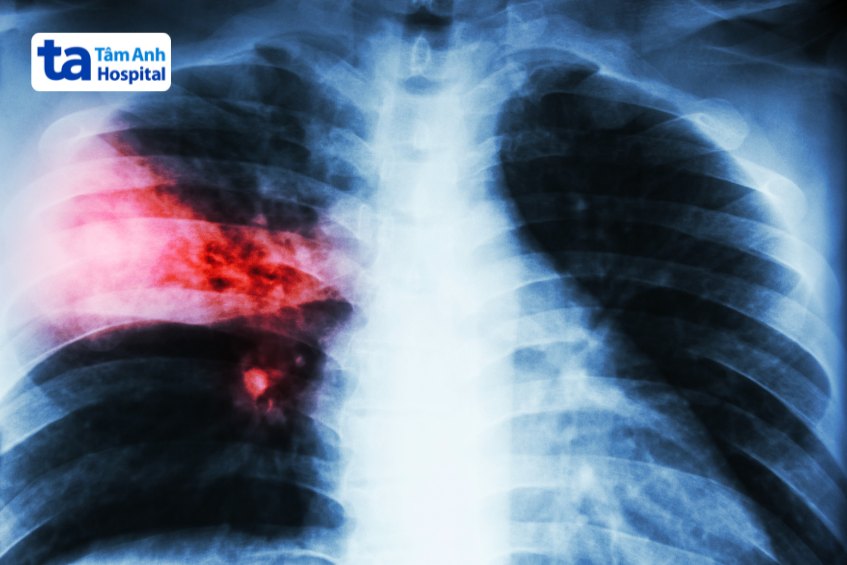

Thông qua hình ảnh chụp X-quang để nhận biết tình trạng các mô, xương và các cơ quan bên trong để xác định vấn đề hô hấp trẻ gặp phải cũng như là mức độ tổn thương ở phổi.

Ở giai đoạn này các dấu hiệu bệnh thường gặp ở trẻ là sốt cao đột ngột, đau tức ngực, ho khan, rối loạn tiêu hóa,… Ở một số trẻ có thể xuất hiệu co giật. Trong vòng 24 giờ sau khi bị nhiễm trùng, vi khuẩn xuất hiện với số lượng lớn trong phổi, trong khi đó, lượng bạch cầu có sẵn để chống lại nhiễm trùng lại rất ít. Lúc này các mô phôi bị sưng và phổi chuyển dần sang màu đỏ do viêm và lưu lượng máu tăng lên.